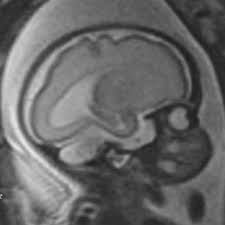

C'est super vieux ces images, il a 62 ans aujourd'hui

Il n'y avait pas les IRM à cet époque